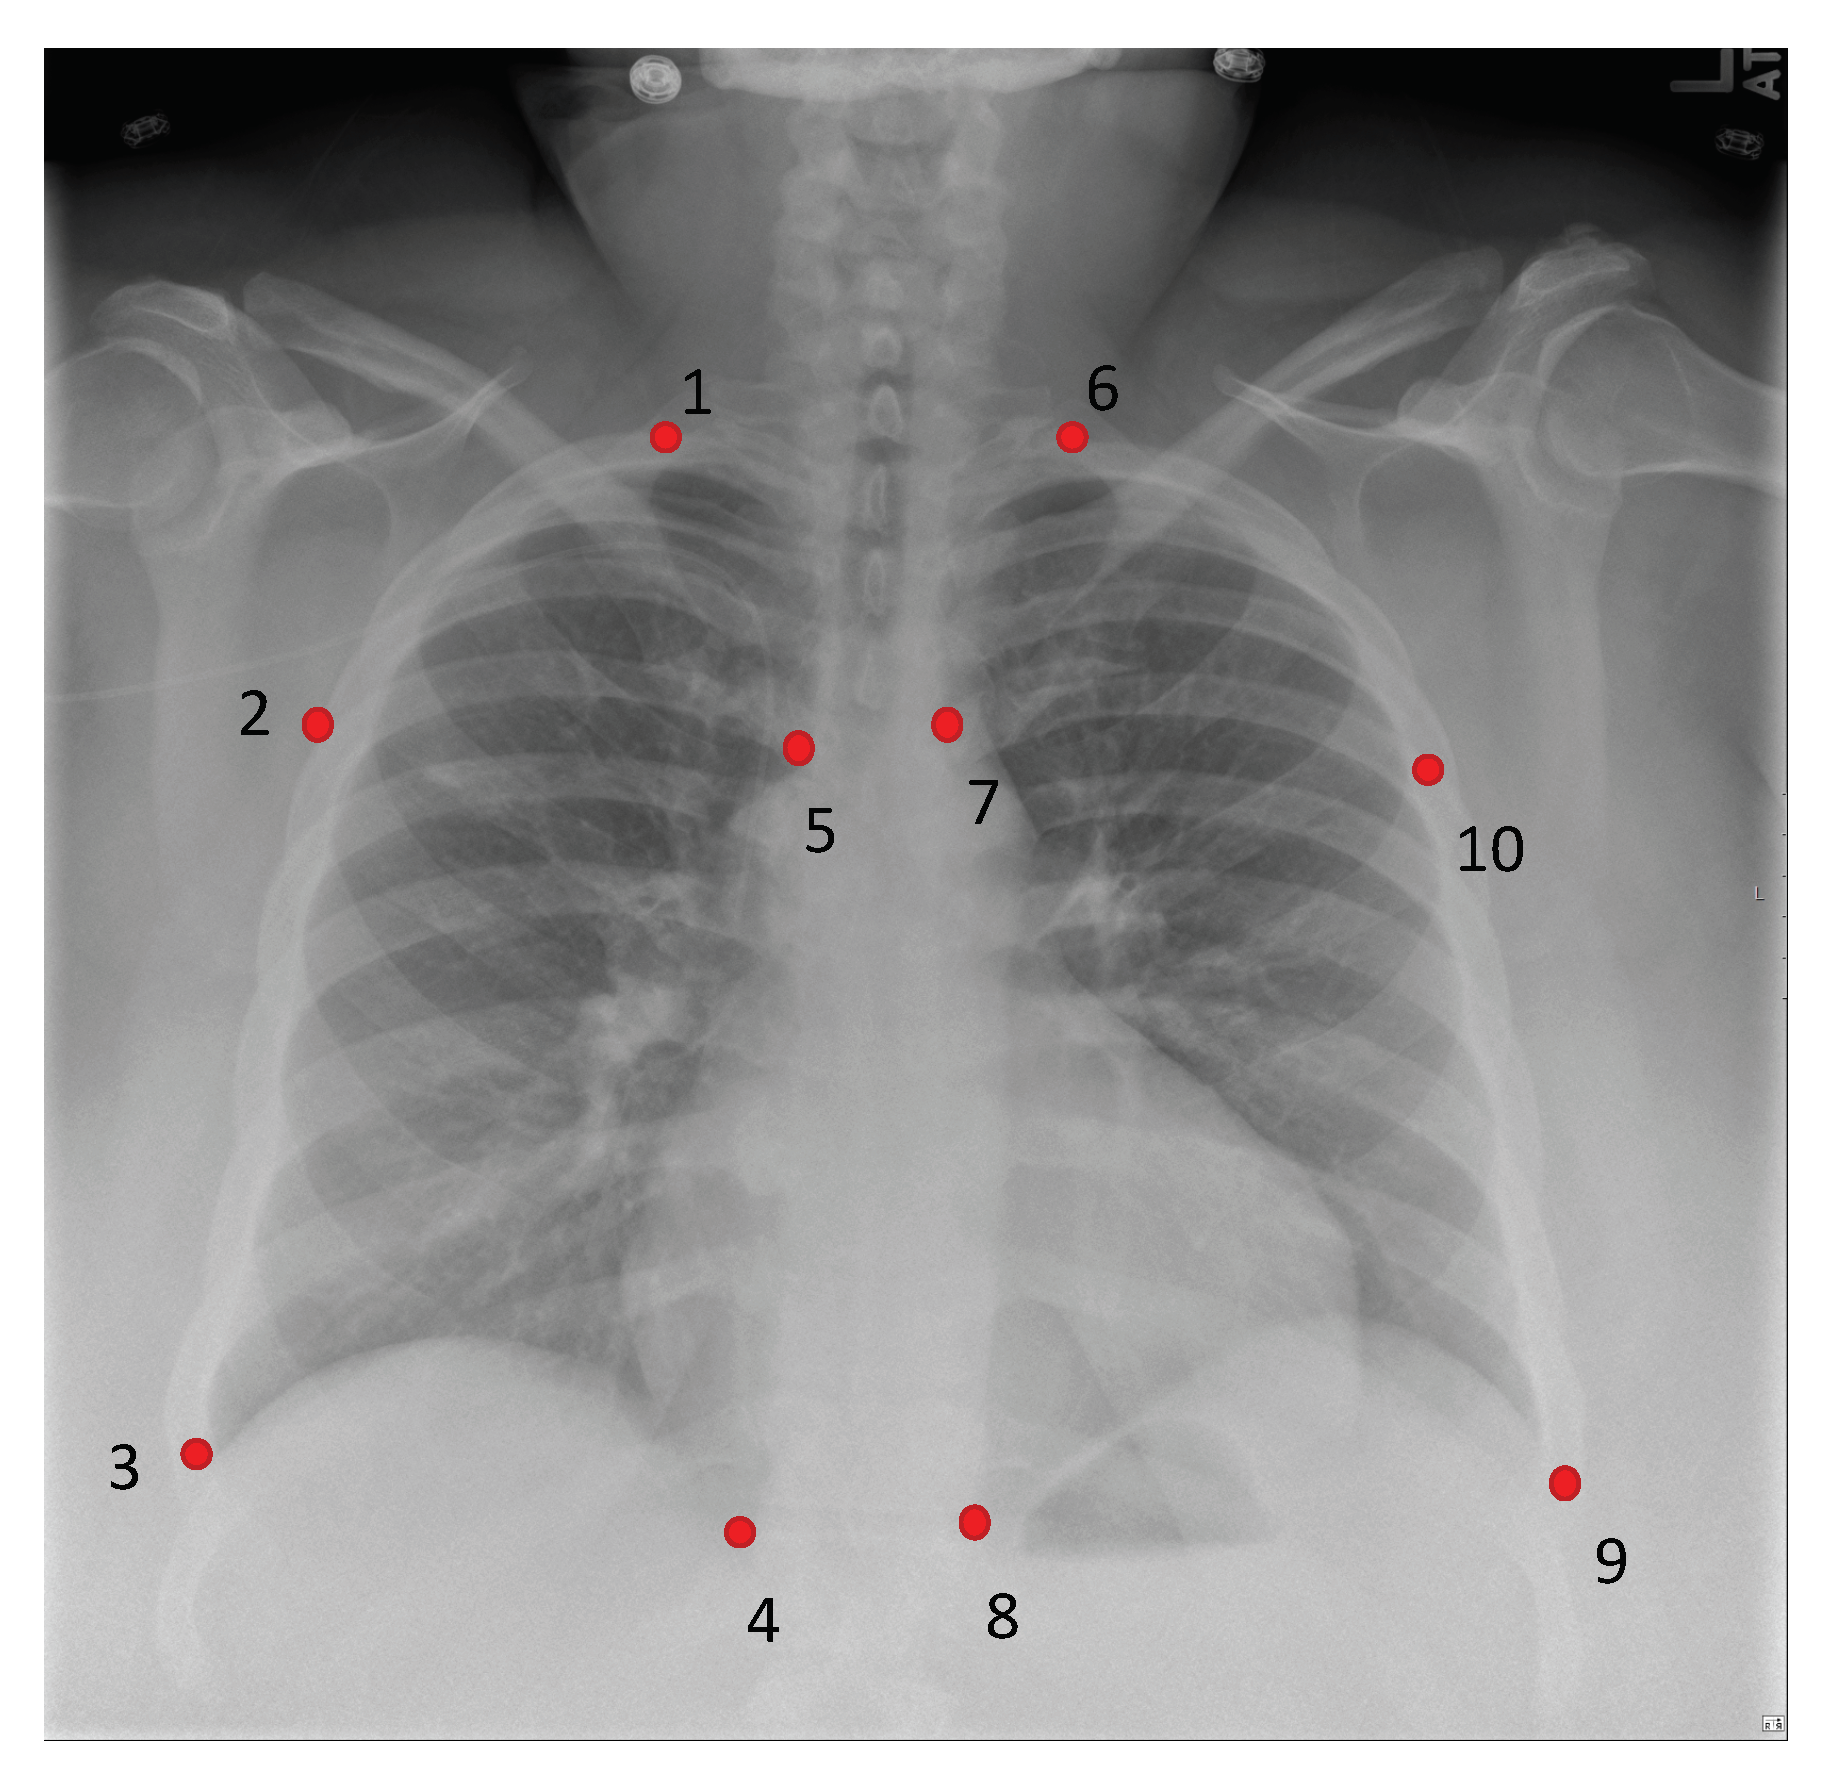

| P1 | 27.995/0.970 | 28.780/3.338 | 0.675/0.195 | 0.723/0.086 |

| P2 | 28.079/1.126 | 29.911/2.783 | 0.756/0.065 | 0.763/0.062 |

| P3 | 28.196/1.290 | 30.025/3.031 | 0.669/0.187 | 0.736/0.101 |

| P4 | 27.960/0.672 | 30.519/2.453 | 0.706/0.076 | 0.795/0.051 |

| P5 | 27.898/0.538 | 29.007/2.444 | 0.683/0.077 | 0.736/0.084 |

| P6 | 28.159/1.097 | 28.523/3.328 | 0.699/0.153 | 0.720/0.098 |

| P7 | 28.407/1.143 | 29.576/2.354 | 0.733/0.070 | 0.778/0.059 |

| P8 | 28.595/1.786 | 31.005/2.201 | 0.776/0.063 | 0.802/0.052 |

| P9 | 28.075/0.826 | 30.485/3.503 | 0.721/0.079 | 0.737/0.134 |

| P10 | 27.940/0.676 | 30.738/2.589 | 0.713/0.070 | 0.767/0.067 |